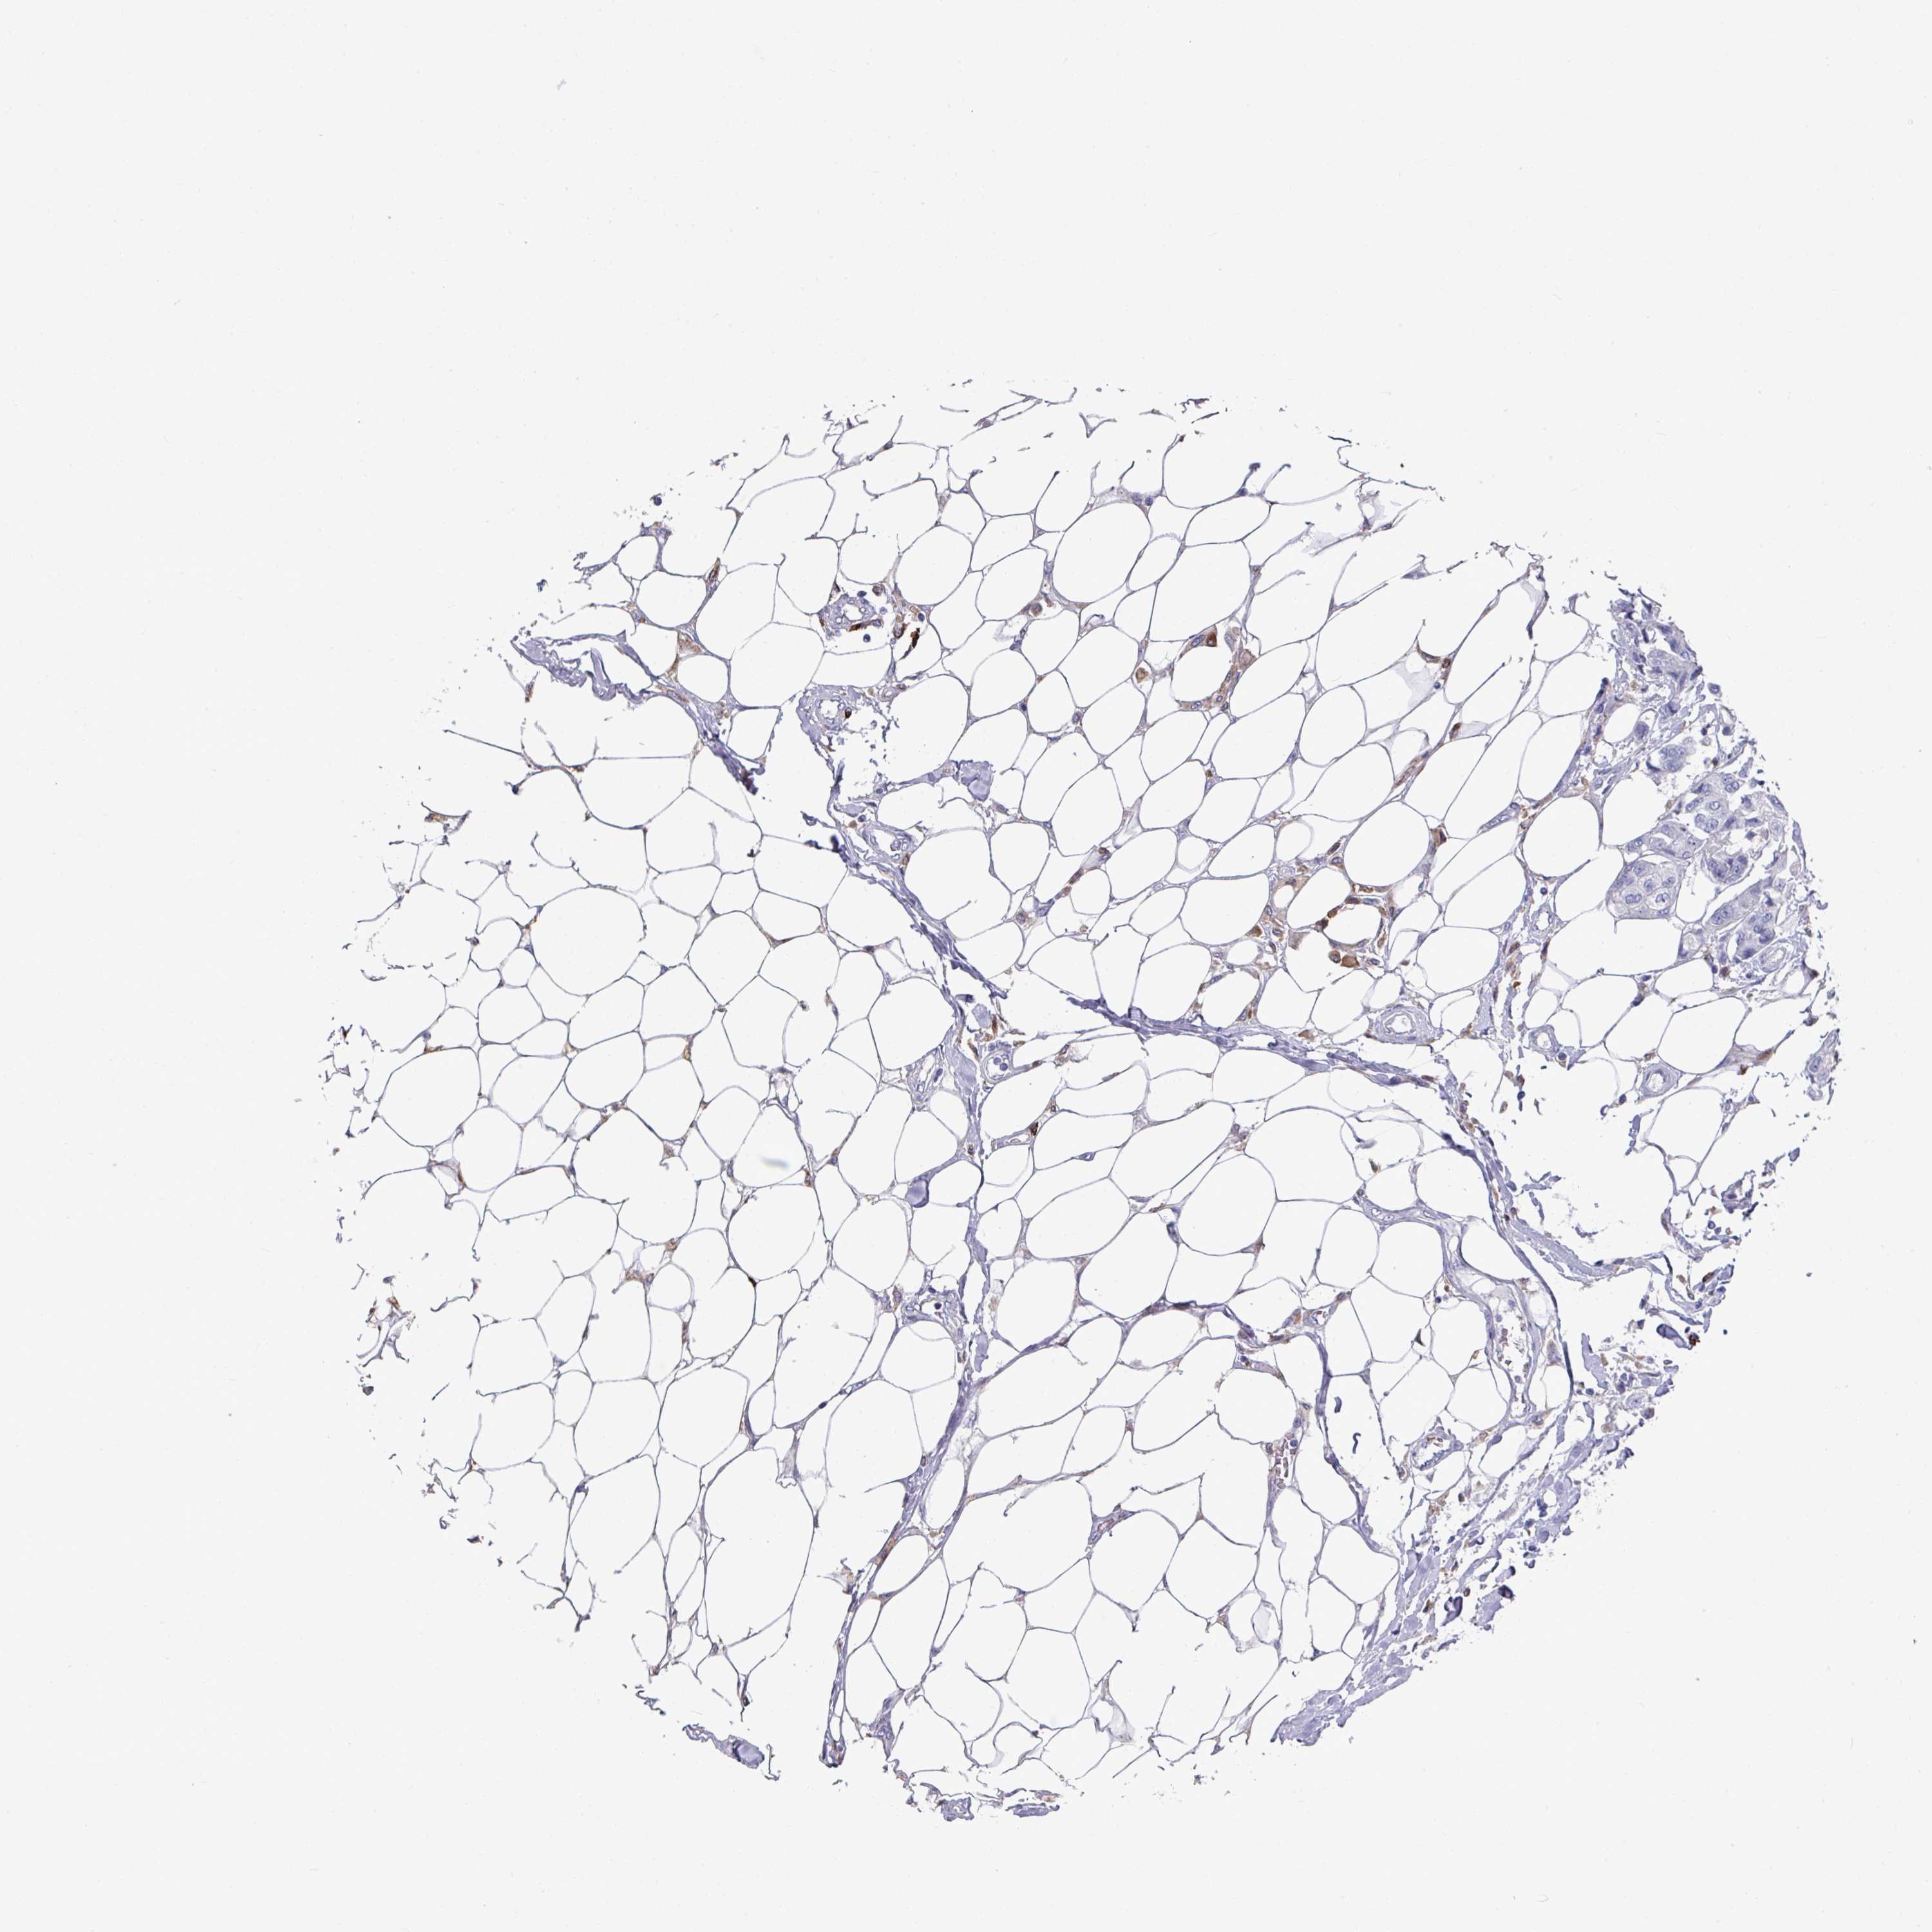

CANCER BREAST CANCER Show tissue menu

BRCA TCGA BRCA VALIDATION PROTEIN EXPRESSION